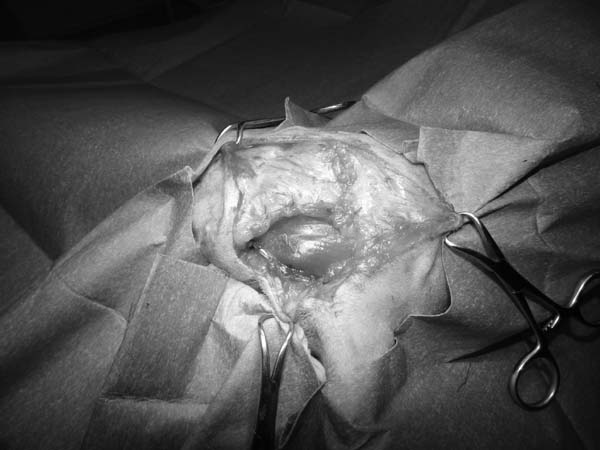

5~6歳以上の去勢手術をしていないオス犬に多い病気ですが、メス犬や去勢した犬に起こることもあります。お尻の筋肉が萎縮した結果、筋肉の隙間から直腸や膀胱が皮膚の下にとびでてしまいます。これにより便が出にくくなったり膀胱炎になったりします。手術をすることで機能回復および今後の致死的な状況を回避することができます。当院では去勢手術→結腸固定→前立腺固定→骨盤隔膜構成筋の縫縮→内閉鎖筋フラップ→浅臀筋フラップの順で通常腹側・臀部左右両側同時に行います。また老化以外に、筋肉が萎縮する原因があったり、腹圧がかかる原因があったりする場合も多いので、再発防止のためそれらの診断・治療も重要です。今回のワンちゃんも無事手術も終わり元気に退院しました。よかったね。